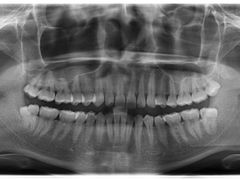

• 德伦口腔

• -德伦口腔